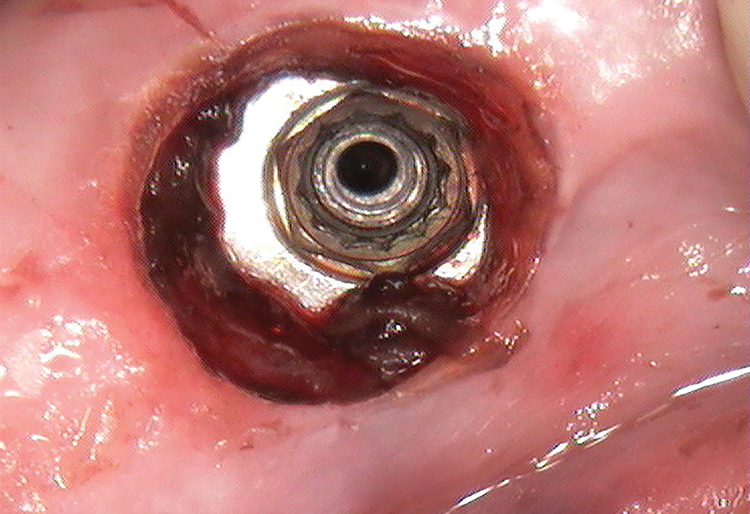

Once anesthesia was achieved, a periodontal probe was used to identify the extent of the implant platform, and then an appropriately sized biopsy punch was used to access the implant (Figure 4). Following access, a presoak of tartar and stain remover was injected into the fixture for a period of 10 minutes. This helped to remove any debris and corrosive elements that may have contributed to the difficulty of retrieval (Figure 5). A 0.36-mm capillary suction tip was used to remove the solution, and a new volume was deposited to penetrate the fixture as needed.

After the soak was complete, an ultrasonic tip was used with copious irrigation in a counterclockwise motion in short intervals to further loosen the screw fragment. The short intervals helped to reduce the amount of heat produced while still providing efficacy. After several rounds with the ultrasonic tip, a 25-gauge metal cannula was used to engage the top of the screw fragment and help rotate it in a counterclockwise direction. This use of the cannula was alternated with the ultrasonic tip to gain adequate movement of the fragment (Figure 6). Once the screw fragment was able to be retrieved, it was removed with the narrow suction tip (Figure 7). A healing abutment was then placed to contour the tissue until adequate healing occurred.